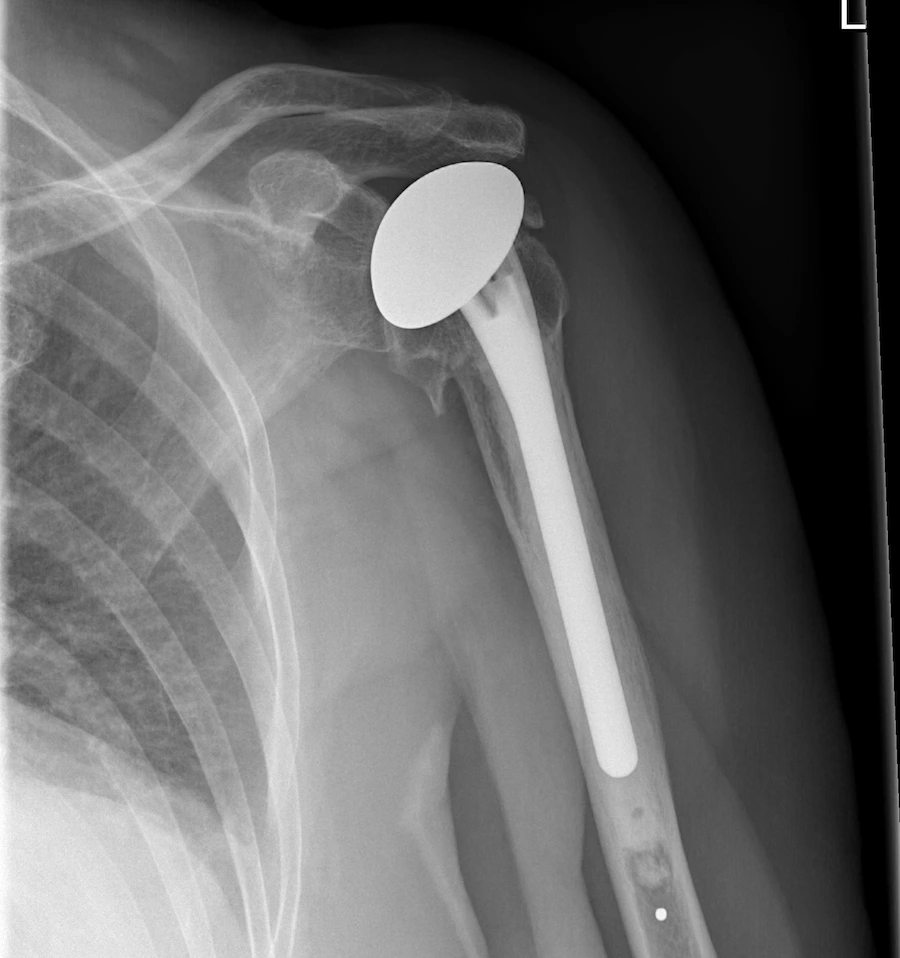

- Total (TSA) and reverse (rTSA) shoulder arthroplasty are common for arthritis, chronic rotator cuff tears, or traumatic injury.

Successful shoulder replacement recovery depends on restoring balanced movement through the ribs, neck, and upper back—not just the joint itself. Public Domain Xray (Lucien Monfils 2011)